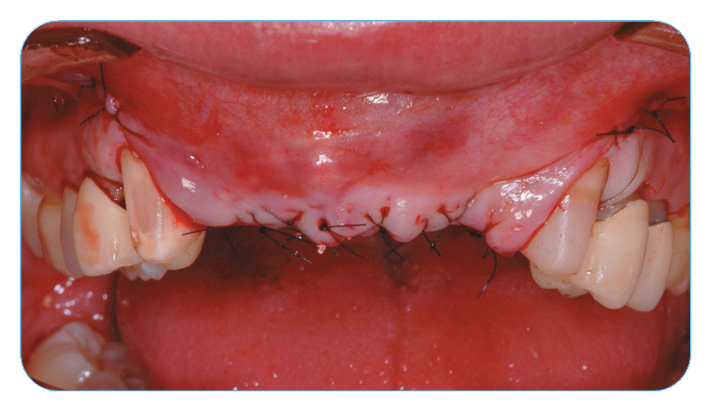

Anterior Ridge Augmentation

Fig. 3. The soft-tissue flaps were closed and sutured.